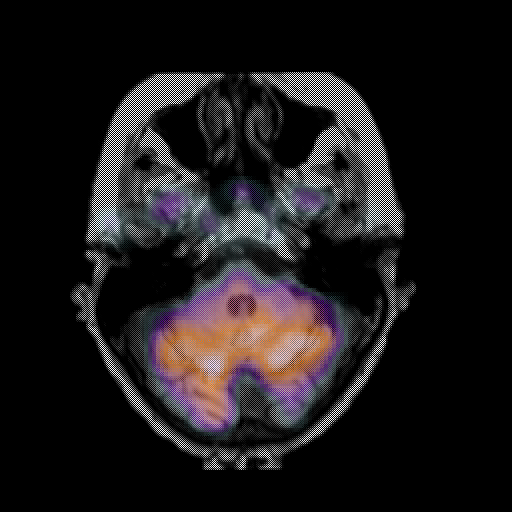

overlay: Slice 13

Slice 13

MRCBFCBF with

T1PDT2T1PDT2